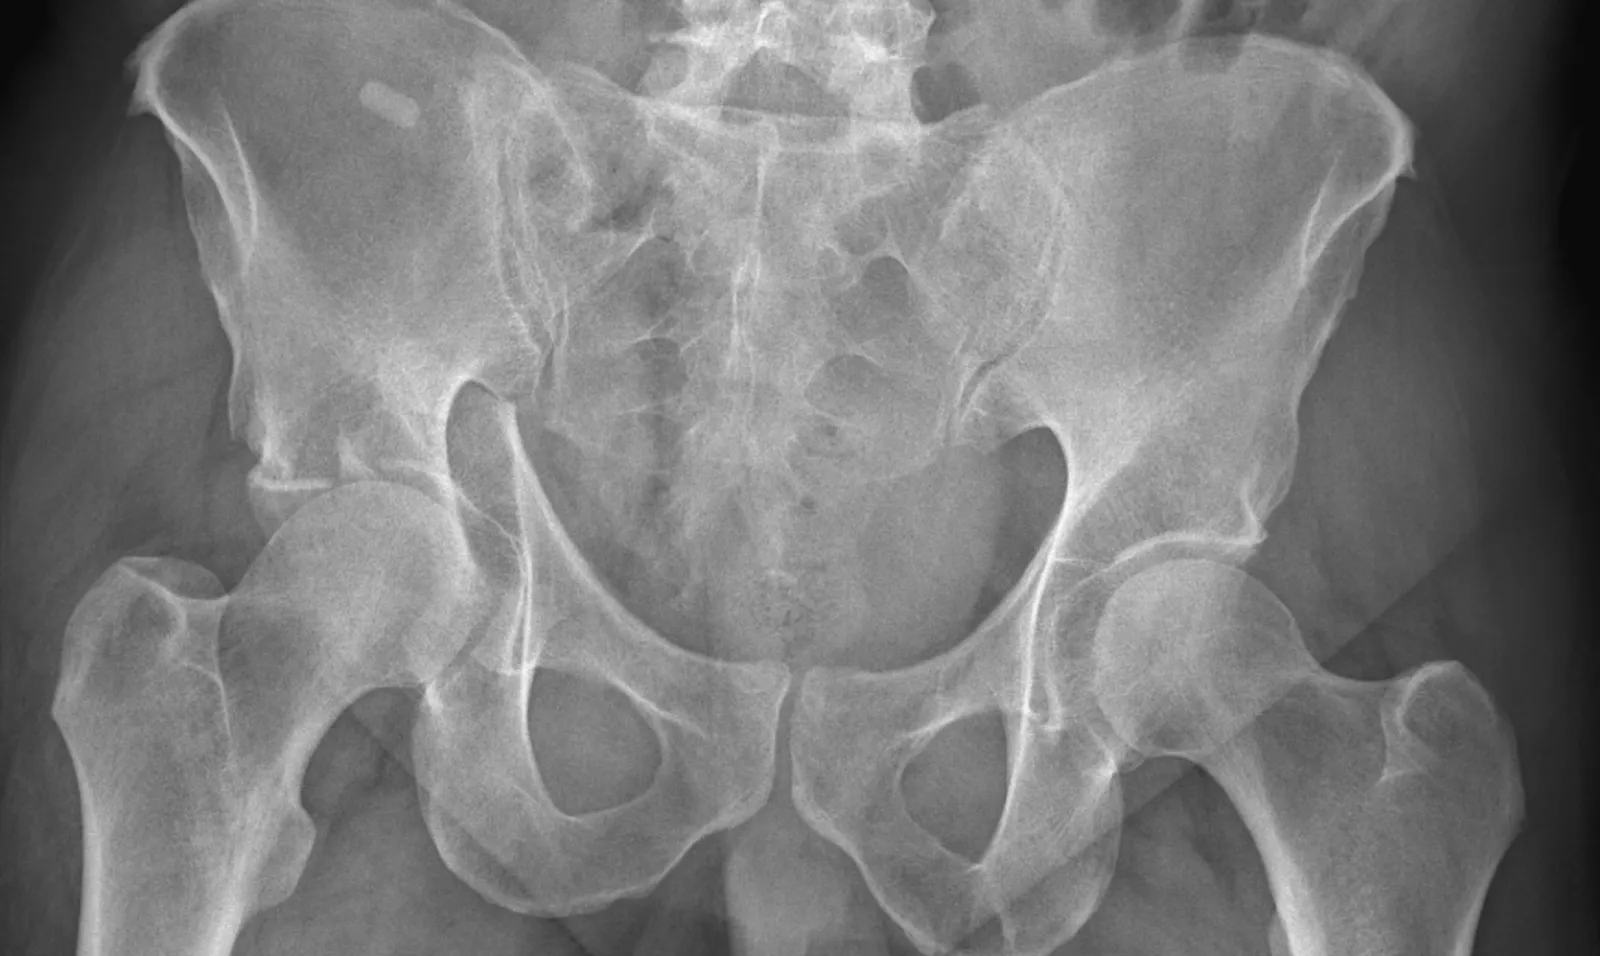

"My story started about six years ago, while playing tennis I fractured my Acetabulum in Florida. It took 10 screws, a lengthy recovery and rehab before I was able to resume my activities. However, I continued to have a level of discomfort and pain in my hip. About two years ago, the pain had gotten so severe that walking was extremely painful, I could not sit for any length of time and I found myself having to limit my activities. Both my wife and I are outdoors people, we love to hike, kayak, bike and boat; I could no longer do these things."